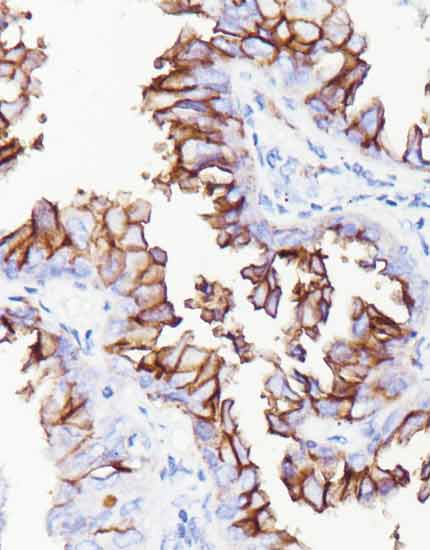

产品名称:c-Met

产品编号:RMA-1039

阳性部位:胞膜/胞质

图片描述:

肺腺癌,c-Met染色,细胞膜/细胞质阳性